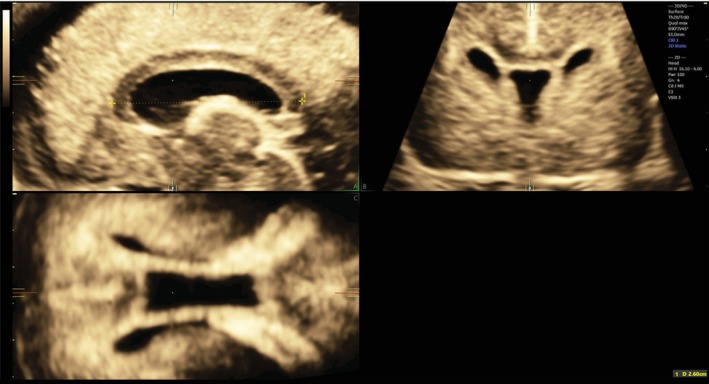

Methods: This was a cross-sectional multicenter retrospective study based on 3D volume dataset acquisitions of the fetal CC between the 15th and 37th weeks of gestation. Only volume datasets acquired transvaginally through the anterior fontanelle were selected. After plane alignment on multiplanar imaging, the length of the CC was measured edge-to-edge on magnified images. Intra- and interobserver variability were assessed and the related intraclass correlation coefficients (ICC) calculated. Biometric charts to assess the reference values for fetal CC were obtained using the method proposed by Altman in 1993.

Abstract Image